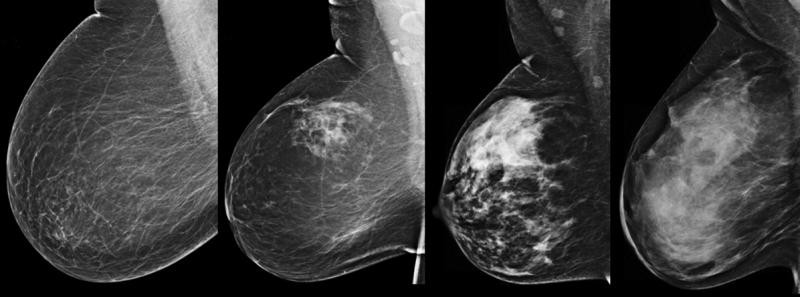

The practice of breast imaging and screening in women at risk for breast cancer is evolving as new imaging modalities ...

Breast mammography has become the standard diagnostic breast screening tool in women’s healthcare, aiding in the ...